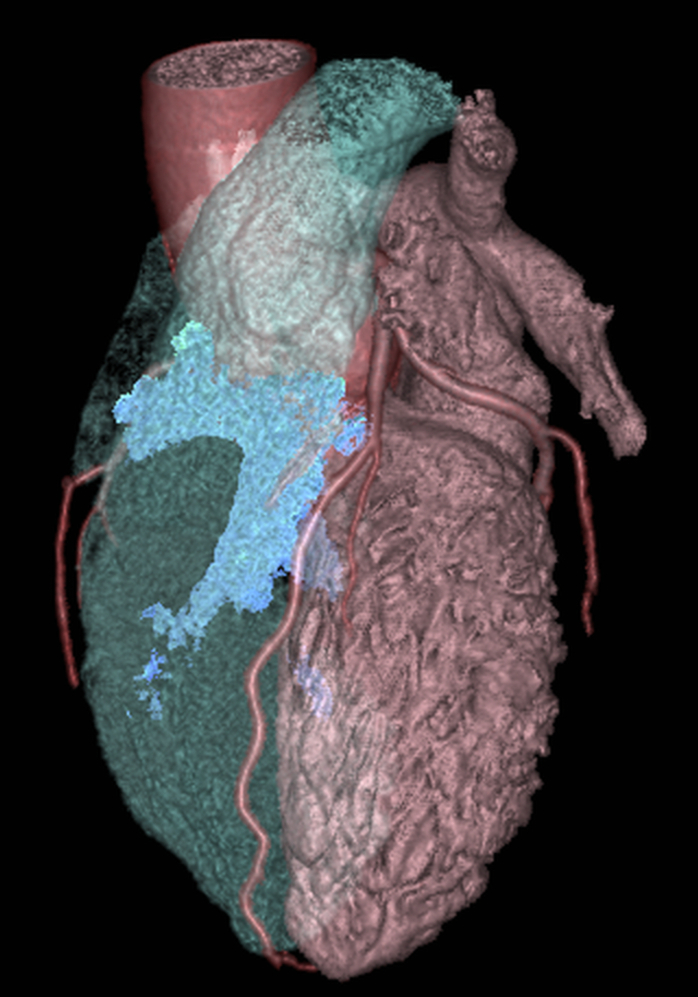

En cardiovasculaire, le CHU de Rouen est reconnu au plan national pour l’exploration du cœur par le scanner et l’IRM. L’unité d’imagerie cardiovasculaire est partie prenante de l’Institut Alain Cribier des Valves Cardiaques et de la plateforme de recherche MiraclAI. Nous disposons de matériels haut de gamme et d’une équipe médicale et para médicale étoffée attirant de nombreux étudiants. Les thématiques de recherche incluent les maladies valvulaires cardiaques et l’étude des cardiomyopathies, notamment la Maladie de Fabry.

• Le scanner: Nous pratiquons le scanner pour le dépistage et le traitement de la maladie coronaire, pour le bilan pré opératoire des valvulopathies aortiques (TAVI notamment) ou mitrales, des aortopathies thoraciques et abdominales ou pour le suivi des cardiopathies congénitales. Dans le domaine de la prévention cardiovasculaire, le score calcique est disponible sur les sites de Charles-Nicolle et Bois-Guillaume.

Scanner stenose coronaire